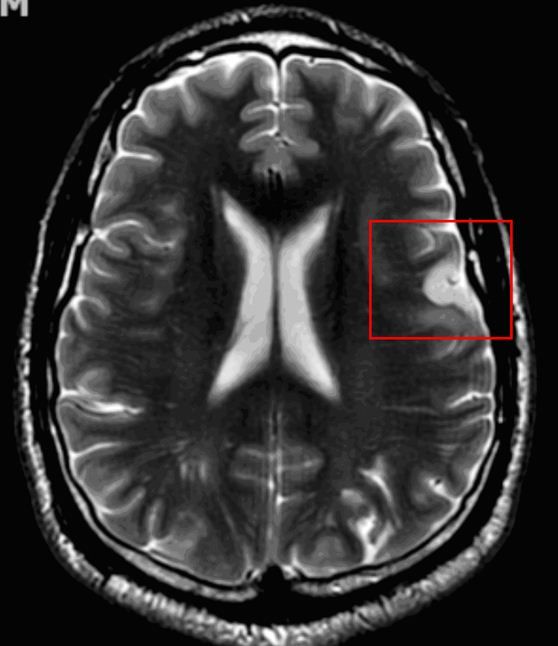

A 42-year-old man presented to the ED after experiencing multiple episodes of difficulty in speaking. Three years earlier, he had a DVT that was treated with anticoagulation. He had also sustained head trauma without loss of consciousness approximately 4 years earlier. The patient was a competitive bicyclist and maintained a rigorous training regimen. CT angiography of the head was unremarkable and MRA of the neck with contrast found no signs of stenosis, thrombosis, or dissection. MRI of the brain with contrast indicated a subacute infarct.